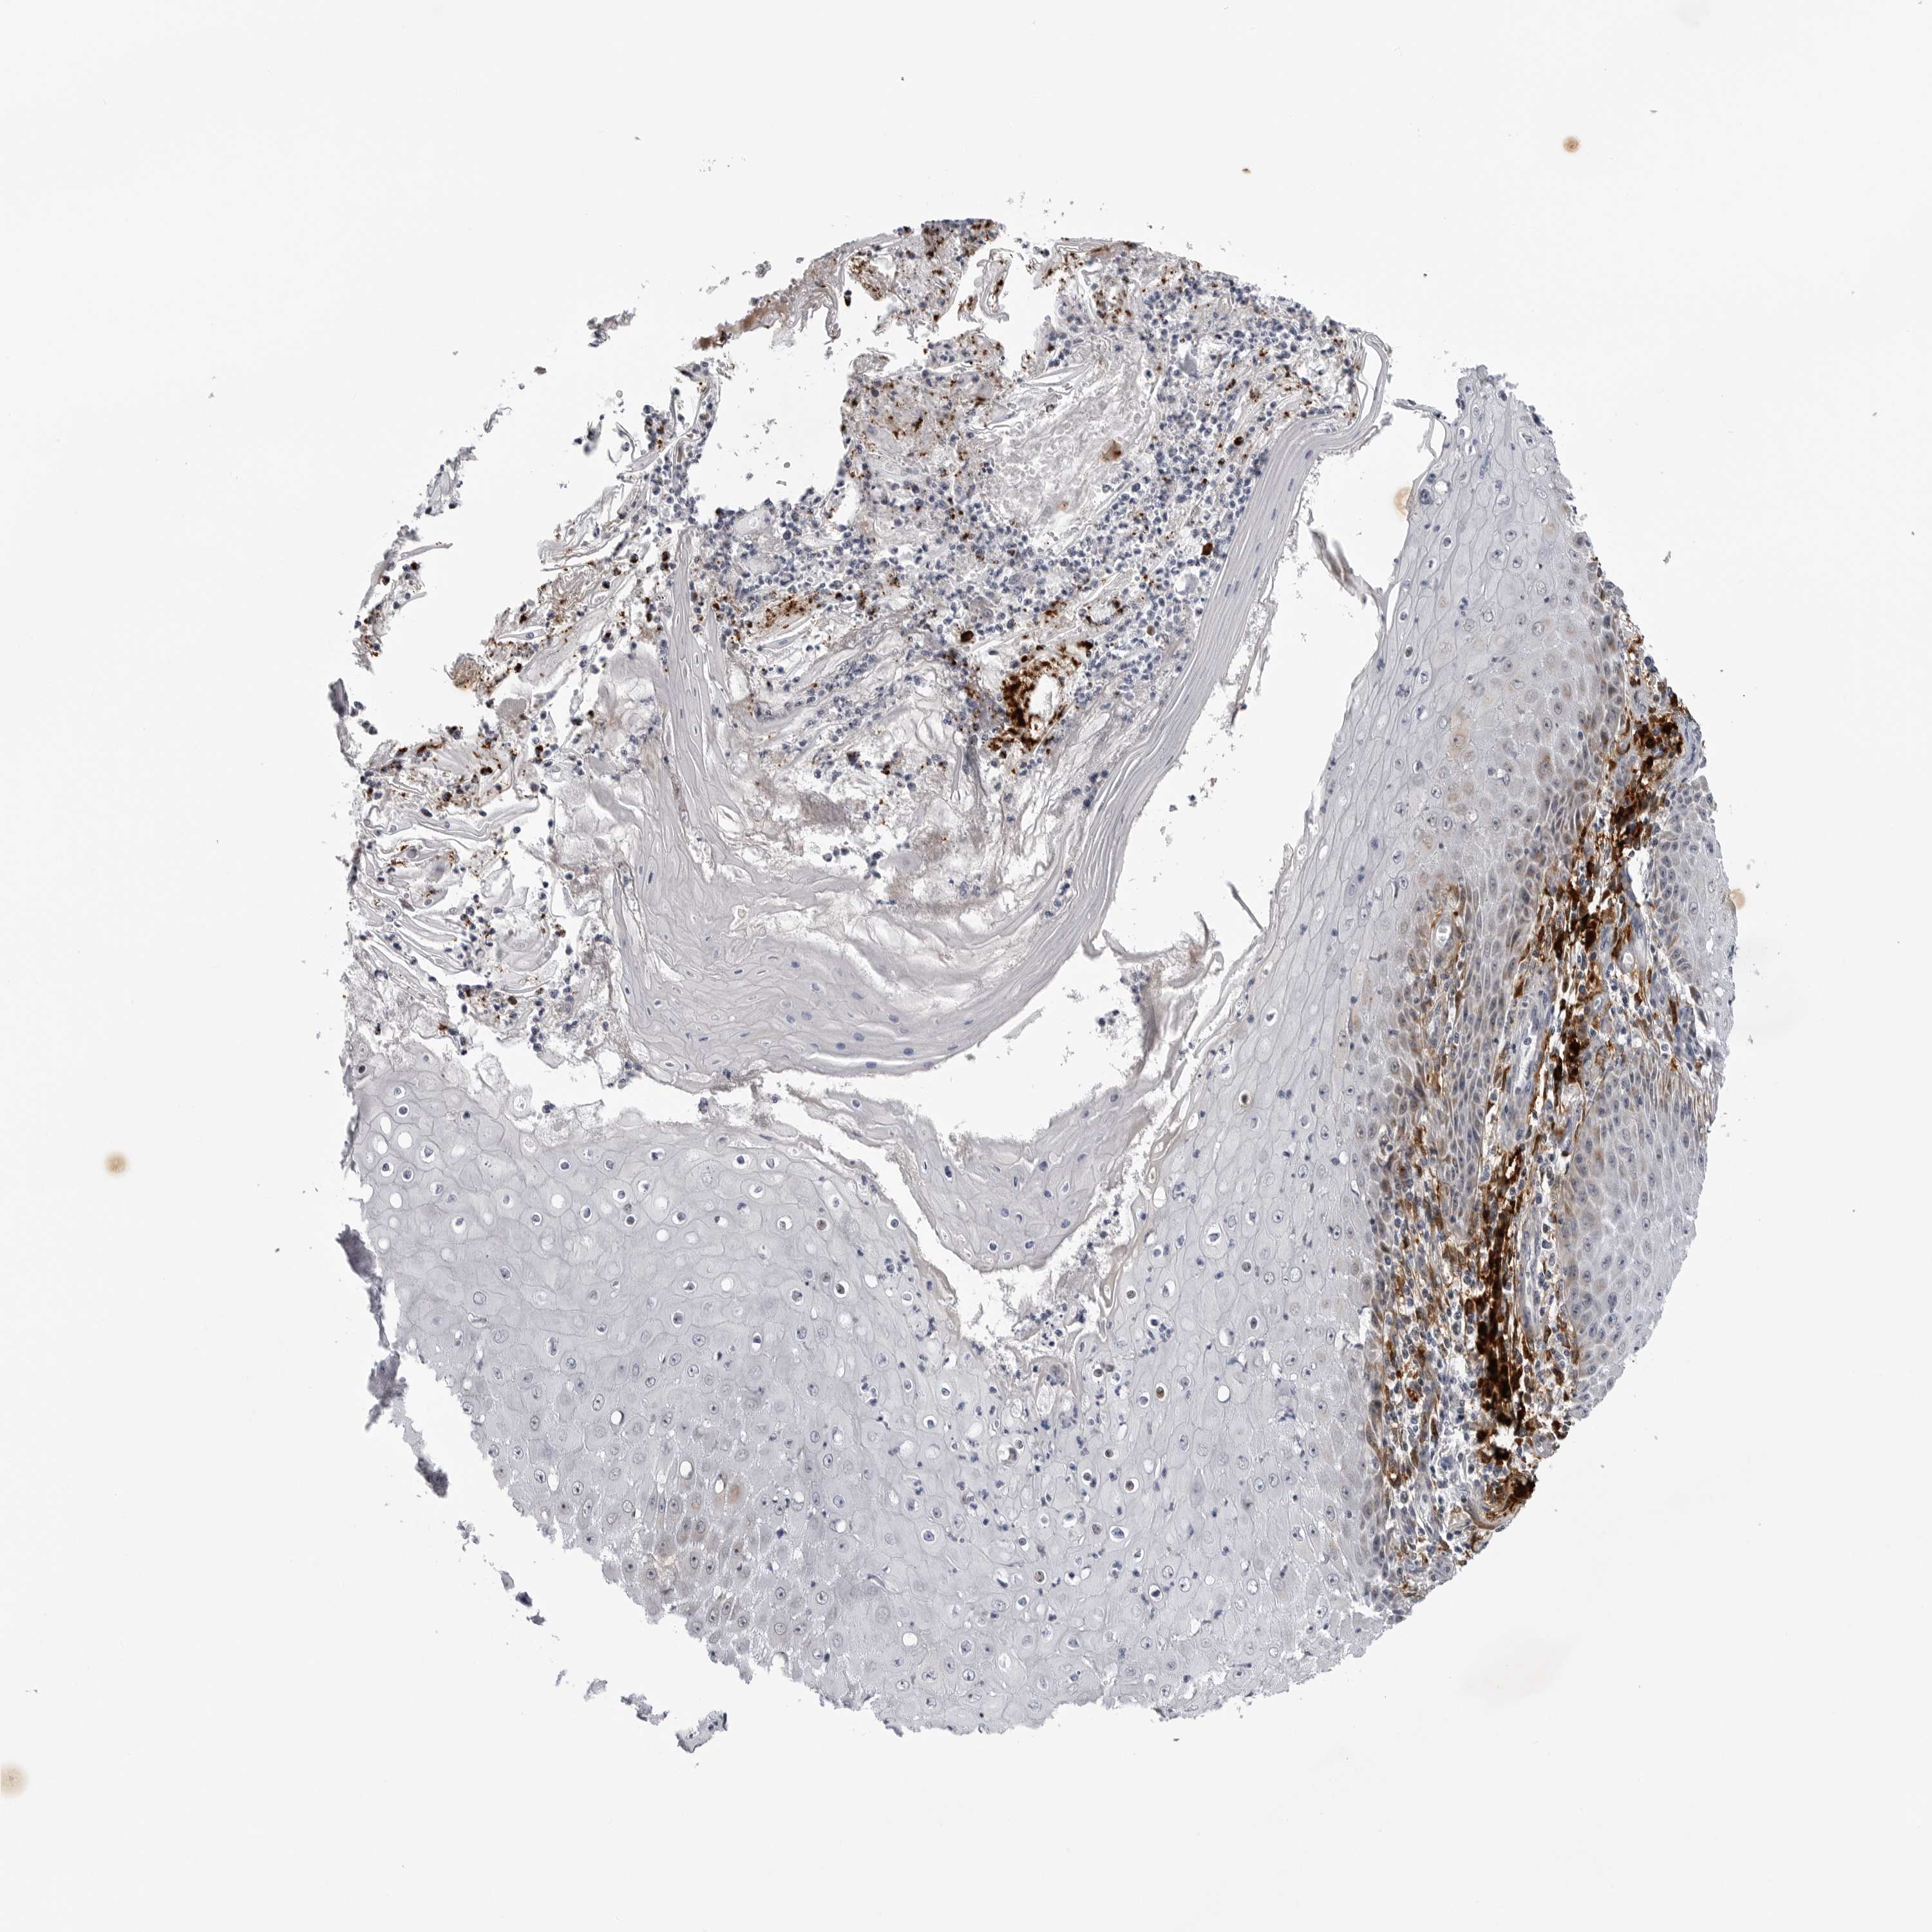

SKIN CANCER - Protein expressioni

A mouse-over function shows sample information and annotation data. Click on an image to view it in a full screen mode. Samples can be filtered based on level of antibody staining by selecting one or several of the following categories: high, medium, low and not detected. The assay and annotation is described here.

Each image is clickable and will lead to virtual microscopy that enables deeper exploration of all samples and also displays staining intensity scores, fraction scores and subcellular localization as well as patient and tissue information for each sample.

Antibody HPA027401

Squamous cell carcinoma, NOS